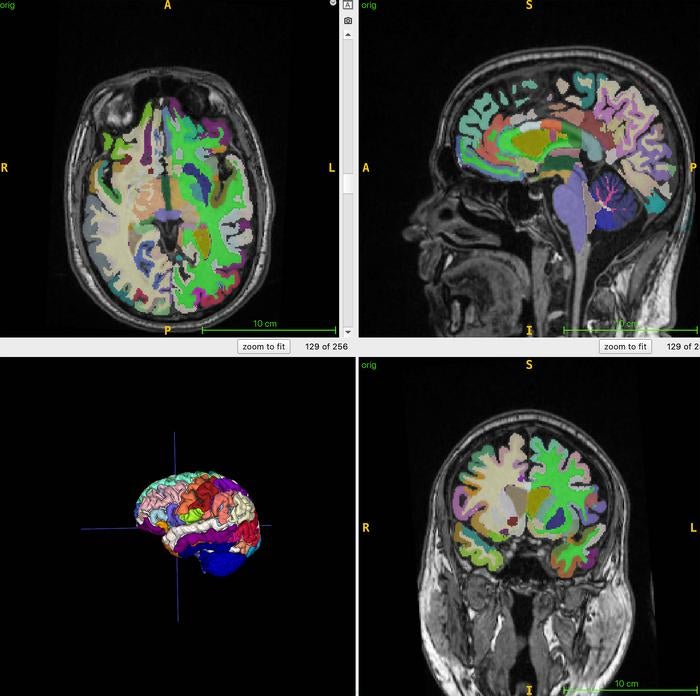

Looking at the health of 1,164 healthy men and women using whole-body MRI scans, the researchers were able to determine the fattiest parts of the body. Next, they used an AI algorithm to determine the participants’ ratio of muscle to fat, as well as their subsequent brain age.